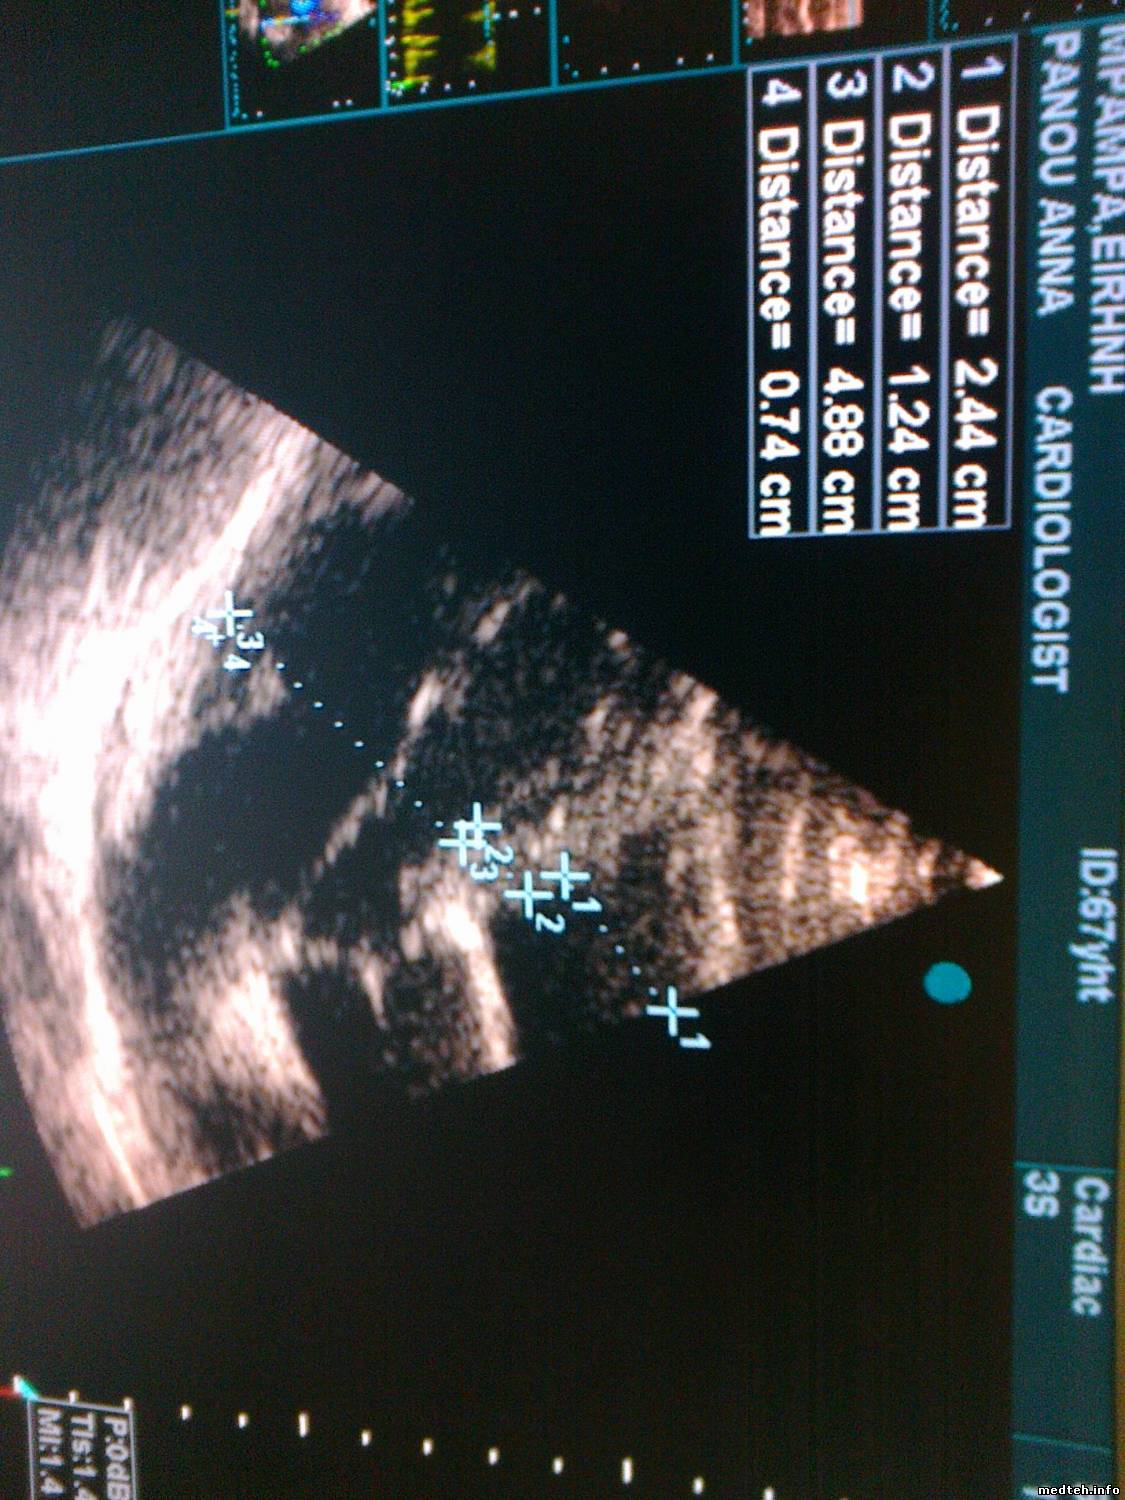

после 5 лет работы качество изображения ухудшилось.

пробовал другой датчик-тоже самое.

тоже самое и при других программах(кардио и тд).

Может кто- нибудь встречал такую проблемму на vivid3?

прилагаю photo

kapamed, посмотрел фотку... а в чем собственно проблема?

ADIDAS- исчезла чёткость, мягкость, появились помехи в виде снега.

менял настройки-всё равно не важное изображение.

на других vivid3 при таких-же параметрах настройки, изображение гораздо лучше